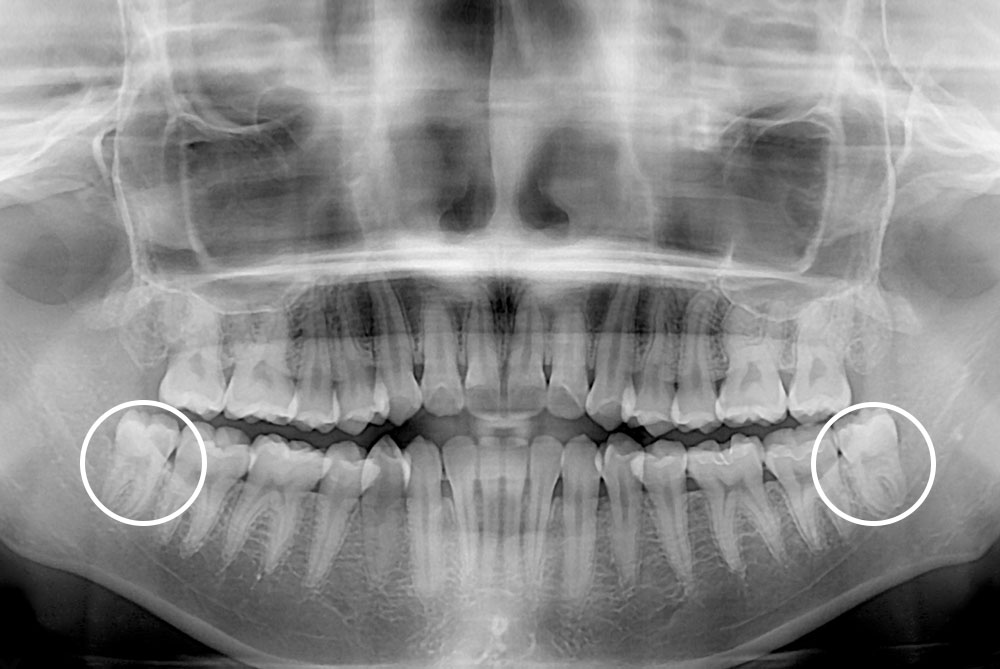

[사랑니] 매복 사랑니 발치

치료후 : 2019-07-27

세종치과는 구강악안면외과학 박사이신 원장님이 발치하는 치과입니다.